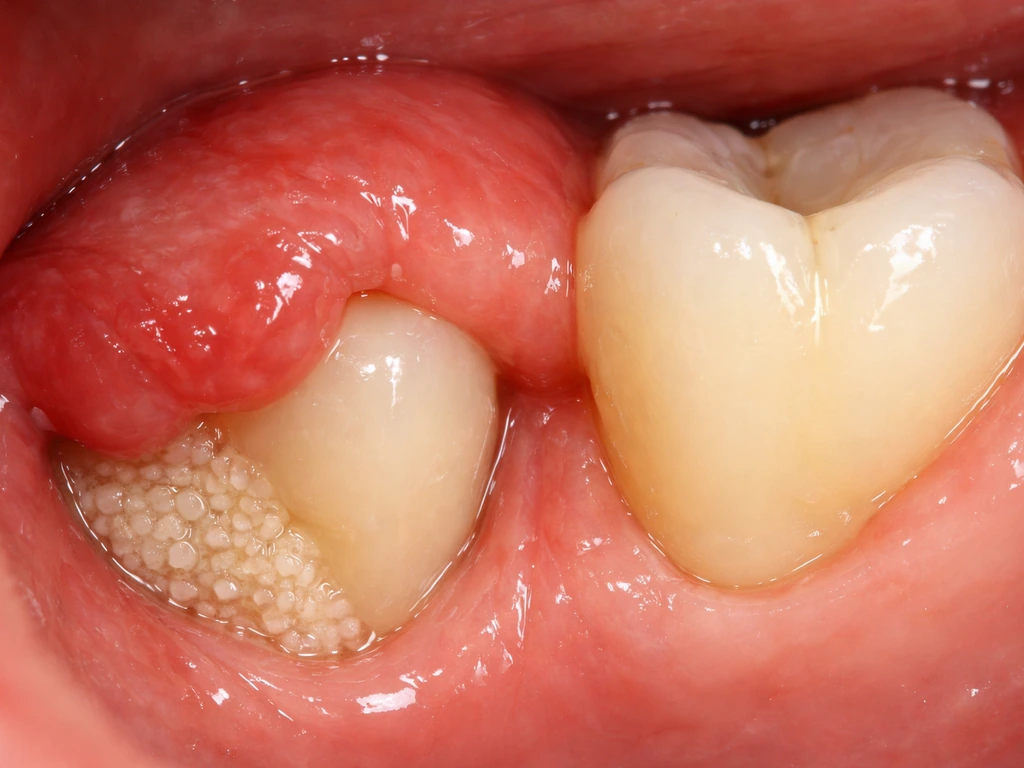

Operculectomy for wisdom teeth

If a wisdom tooth is partially erupted but a thick flap of gum (operculum) is covering it, a minor surgical procedure can remove that flap and allow the tooth to erupt more cleanly. This is only appropriate when the tooth is actually in a good position and has room to come through, which is not always the case with wisdom teeth.